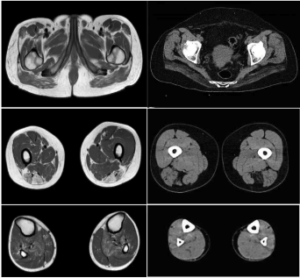

Loss of function variants in DNAJB4 cause a myopathy with early respiratory failure to be published in Acta Neuropathologica